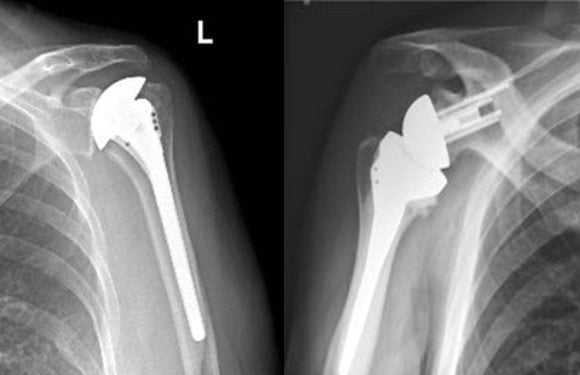

Пациентам с тяжелыми повреждениями плечевого сустава показано эндопротезирование. Замена сочленения искусственным имплантатом позволяет полностью восстановить объем движений, вернуться к активному образу жизни.

Радикальных операций две – артродез и эндопротезирование. В первом случае сустав выключается из активных движений путем плотной фиксации. Это приводит к полному устранению болевого синдрома, но столь же неотвратимо блокирует любые движения в нем. Эндопротезирование – отличный вариант вернуть больному радость движений. Однако в настоящее время протезы применяются ограниченно, только в крупных городах в единичных медицинских центрах. Распространению подобной хирургической тактики мешает сложность операции и низкая обеспеченность протезами небольших мегаполисов.

На последней стадии артроза возникают необратимые изменения костной ткани, поэтому для устранения болей и восстановления подвижности врачи предлагают установку эндопротеза. При этом происходит замена больного сустава на титановый или другой имплант.

Вернуться к активной и привычной жизни поможет более эффективный способ хирургического воздействия при деформирующем артрозе плечевого сустава. Эндопротезирование – это сравнительно молодой вид оперативной коррекции, который позволяет заменить атрофированный больной сустав на его искусственный аналог.

Эндопротезы — цементные и бесцементные — различаются способом крепления к кости. В зависимости от заменяемых частей сустава различают два вида протеза:

- гемиартропластика, когда заменяется только головка плечевой кости;

- тотальный протез, когда необходима полная замена плечевого сустава.